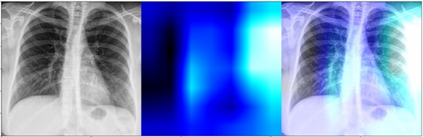

Deep learning (DL) analysis of Chest X-ray (CXR) and Computed tomography (CT) images has garnered a lot of attention in recent times due to the COVID-19 pandemic. Convolutional Neural Networks (CNNs) are well suited for the image analysis tasks when trained on humongous amounts of data. Applications developed for medical image analysis require high sensitivity and precision compared to any other fields. Most of the tools proposed for detection of COVID-19 claims to have high sensitivity and recalls but have failed to generalize and perform when tested on unseen datasets. This encouraged us to develop a CNN model, analyze and understand the performance of it by visualizing the predictions of the model using class activation maps generated using (Gradient-weighted Class Activation Mapping) Grad-CAM technique. This study provides a detailed discussion of the success and failure of the proposed model at an image level. Performance of the model is compared with state-of-the-art DL models and shown to be comparable. The data and code used are available at https://github.com/aleesuss/c19.